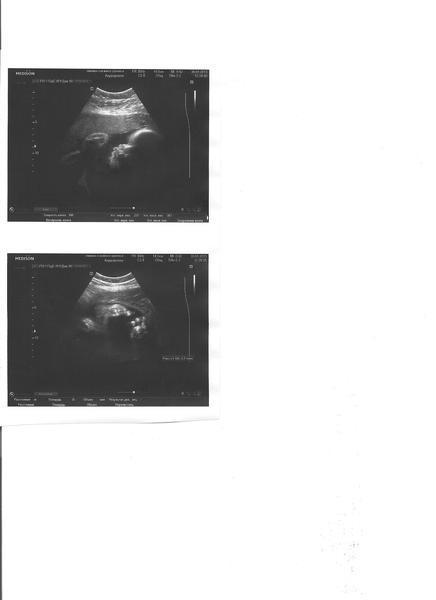

А теперь фотки моей Агаты)))

На первой лицо в профиль, а на второй стопа, и ручка, кот тянется к ней.